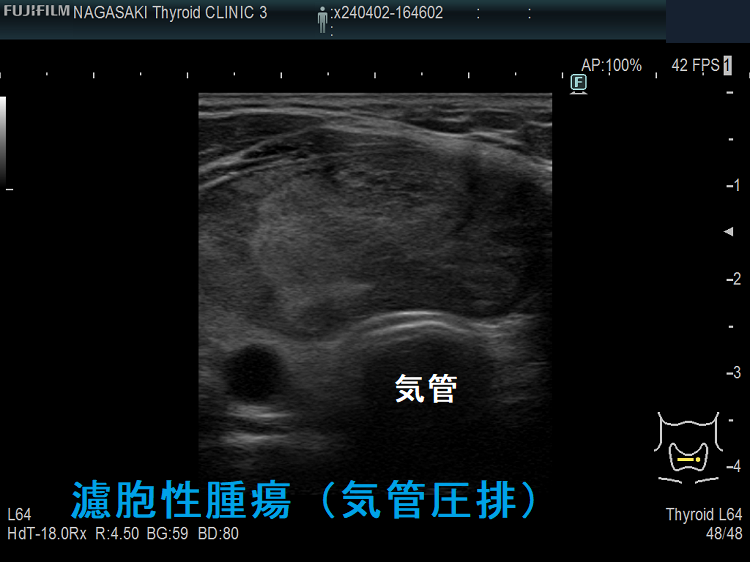

濾胞性腫瘍

のう胞型濾胞腺腫(のう胞腺腫)気管圧排 閉塞性睡眠時無呼吸症候群(OSAS)

のう胞型濾胞腺腫(のう胞腺腫)気管圧排 閉塞性睡眠時無呼吸症候群(OSAS);穿刺排液しても再貯留を繰り返すなら手術切除